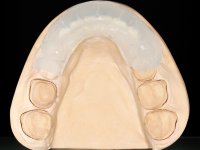

Realizado o diagnóstico e tomada a decisão quanto ao tratamento a executar, tornou-se importante definir qual a sequência de trabalho a adotar no sentido de conseguir a reabilitação da D.V.O. (V.D.O), de forma progressiva e equilibrada. Na primeira fase fez-se uma pré-impressão da arcada inferior com silicone tipo “putty” e em seguida realizou-se o preparo dentário de todo o sector posterior. O preparo para os overlays foi feito coronalmente à linha amelo cementaria no sentido de ser o mais conservador possível. A impressão foi feita com técnica de dupla mistura após afastamento gengival realizado com pasta de caulino. A provisória foi realizada com resina composta de polimerização dual. Em laboratório foram realizados os overlays após se ter aberto ligeiramente (1,5mm) a D.V.O. nos modelos montados em articulador semi-ajustável. Simultaneamente o sector antero-inferior foi encerado no sentido de acompanhar este aumento da D.V.O. Também foi confecionada uma chave de silicone translucido para posterior confeção dos provisórios antero-inferiores. Em boca foi primeiro realizada a provisionalização dos dentes anteriores utilizando resina composta previamente aquecida após preparação das superfícies dentárias para a adesão. Foi colocado o dique de borracha para promover o isolamento absoluto e posteriormente foram colados os overlays. Em laboratório foi realizada nova chave de silicone para confecionar os provisórios antero-superiores. Seguidamente em boca foram preparados os seis dentes antero-superiores após colocação do fio de afastamento gengival. Feita a preparação adequada das superfícies dentárias foi realizada a impressão com técnica de dupla mistura e a respetiva provisória. Em laboratório foram confecionadas 6 facetas feldespáticas num modelo de trabalho tipo “Geller”. A provisória foi removida e as facetas foram coladas em boca utilizando um isolamento relativo competente. Esta opção foi tomada em virtude de uma prévia experiencia negativa com a colocação do dique de borracha na mandibula. Após a colagem dos laminados antero-superiores foram dadas 12 semanas para avaliar a adaptação do paciente à nova situação e então iniciar a confeção das facetas antero-inferiores. Após colocação do fio de afastamento gengival. foram feitos os preparos dentários adequados e em seguida foi feita a impressão. Também foi feita a preparação do dente 3.4 que, entretanto, tinha sofrido uma fratura do overlay. As facetas e a restauração do 3.4 foram realizadas num modelo de trabalho tipo “Geller”. Após remoção da provisória, as facetas foram coladas em boca, utilizando um isolamento relativo pelas razões apontadas anteriormente. Após colocação do trabalho o paciente foi reabilitado por outros colegas com um implante na zona do 2.6 e substituição da coroa aparafusada sobre o implante colocado no local do 3.5. Posteriormente surgiram fraturas nos overlays dos dentes 4.7 e 3.7 que foram reabilitados com overlays em Zr.